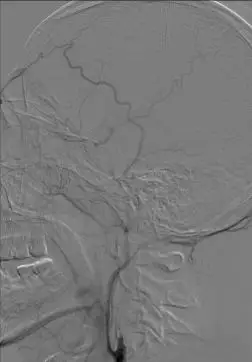

影像学表现与临床症状不匹配,发病超7小时。 DSA: 右侧颈内动脉C1段闭塞;右侧大脑中动脉M1段闭塞,颈外动脉经眼动脉向颅内代偿。

前交通动脉开放,同侧大脑前动脉通过软脑膜支代偿右侧大脑中动脉供血区域。

后循环通过软脑膜支及后交通动脉部分代偿右侧大脑中动脉供血区。

诊断分析 右侧颈内动脉C1段闭塞合并右侧大脑中动脉M1段闭塞。拟行支架机械取栓治疗。 治疗情况 耗材:8F血管鞘,8F导引导管,Navien 5F颅内支撑导管,Rebar-18微导管,0.014微导丝,Solitaire 4-20支架,SpiderFX保护伞,5-40球囊、1.5-20球囊,2-20球囊,9-40 Protégé。 支架: 1. 开通右侧颈内动脉C1: 通过1.5以及2.0球囊对C1段依次进行扩张,可见C1重度狭窄。